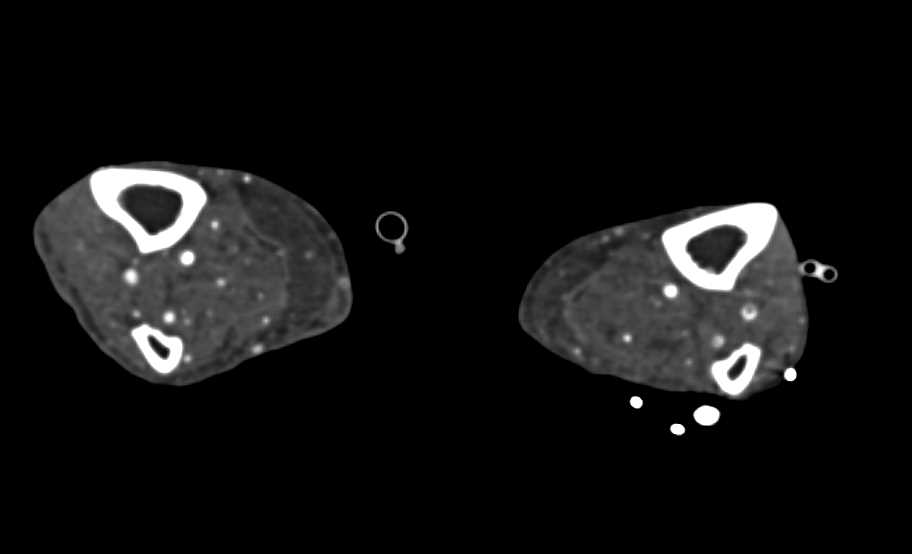

Aortic Aneurysm with Dissection